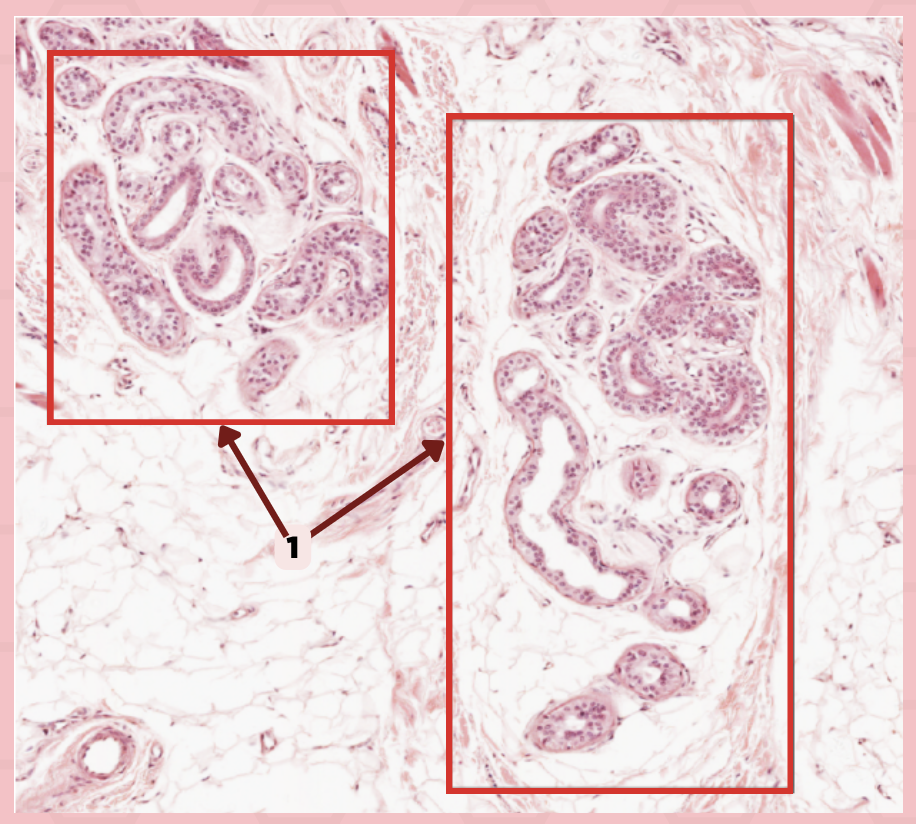

Submandibular

Identify the specimen.

Capsule

Identify the structure labeled as 1.

Septa

Identify the structure labeled as 2.